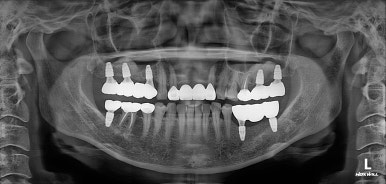

그렇게해서 최종완료 후 치과용 파노라마 사진입니다!

치과치료에 대해 잘 모르시는 분이라 할지라도 보고 있으면, 치료가 조화롭게 잘 끝났구나.. 라고 아실 수 있으리라 생각합니다.

제가 제일 좋아하는 치과용 파노라마 비교 사진입니다.

앞으로 나란히를 한 것 같이 평행한 임플란트의 완성도는 항상 카타르시스를 느끼게 합니다.

정말 어디하나 나무랄 것 없이 치료가 잘 마무리되었는데, 물론 정말 열심히 정성들여 수술하는 저도 칭찬받아야 마땅하지만 늘 묵묵히 열심히 크라운 치료를 잘 해주는 우리 보철과 전문의 원장님들께 그 공을 돌리고 싶습니다.

왼쪽 위 어금니에 2개, 오른쪽 위 어금니에 3개 총 다섯개의 스트라우만 임플란트를 사용하였습니다.

오른쪽 아래 어금니에 2개, 왼쪽 아래 어금니에 1개 (그리고 사랑니 발치까지) 수술이 잘 이루어졌네요!!

마지막에 심었던 오른쪽 위 어금니 임플란트 골유착이 완성되었고, 그동안 나머지 부위들은 임플란트 크라운 치료를 완료 해두었습니다.

상당히 깔끔하게 제작되었고, 기존에 해둔 상악동 뼈이식술도 아주 잘 자리잡아주었네요.